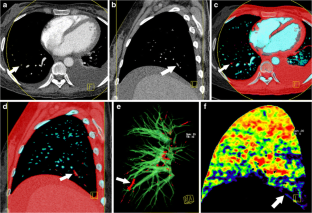

Fig. 2